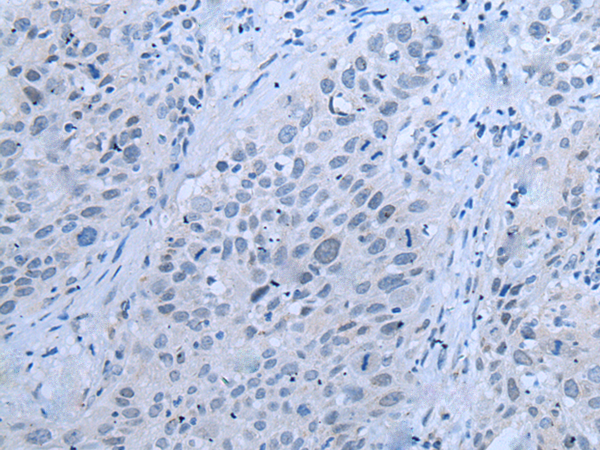

分类: 科研抗体货号: P12833别名:应用: WB,IHC反应种属: Human, Mouse